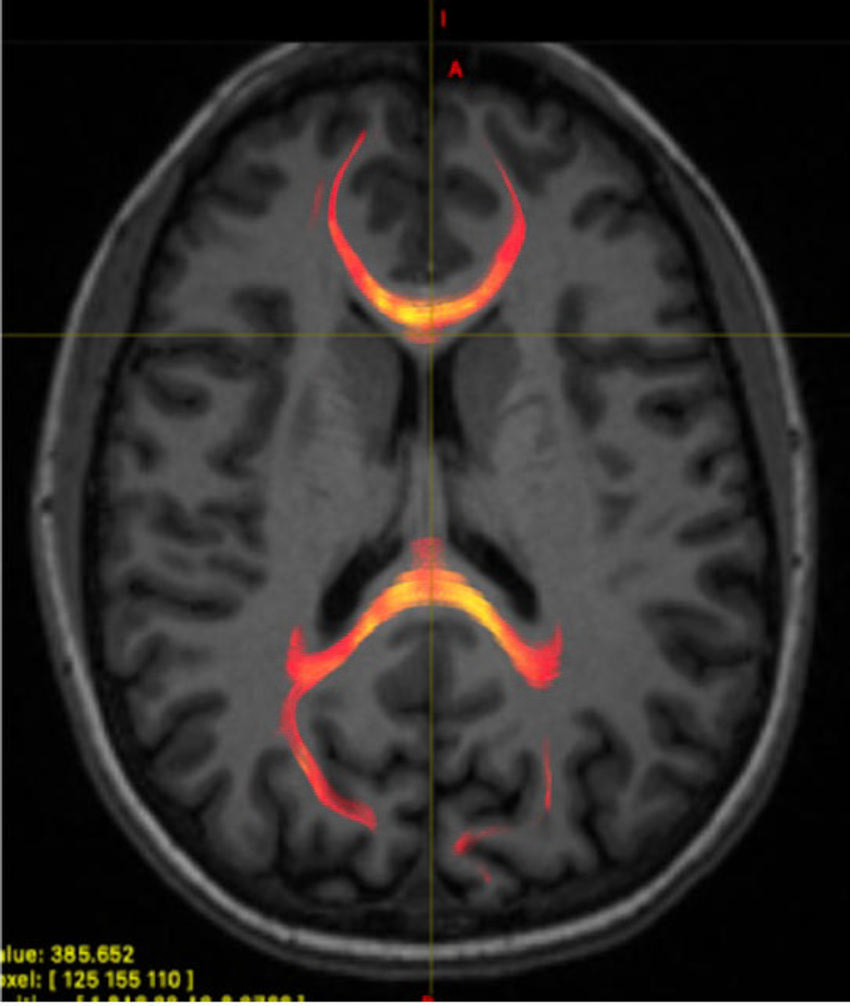

Figure 1. MRI image from a mild traumatic brain injured patient demonstrating corpus callosum fiber tractography, which is a 3D reconstruction of white matter fibers. This image specifically provides information on the axonal water fraction, which was one of the compartment diffusion metrics analyzed.